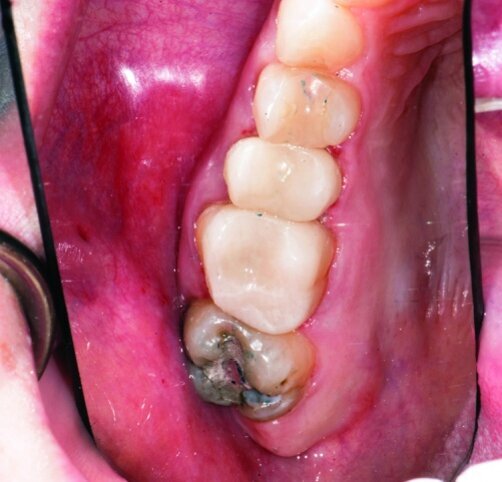

This patient presented for restorations of teeth #3 and #4 (Fig. 1a). Because of the size of the existing restorations, these teeth were diagnosed as structurally compromised (Figs. 1b, c). The prognosis without treatment was fair.

The restorations were to be completed with PlanScan chairside CAD/CAM technology in the same visit.